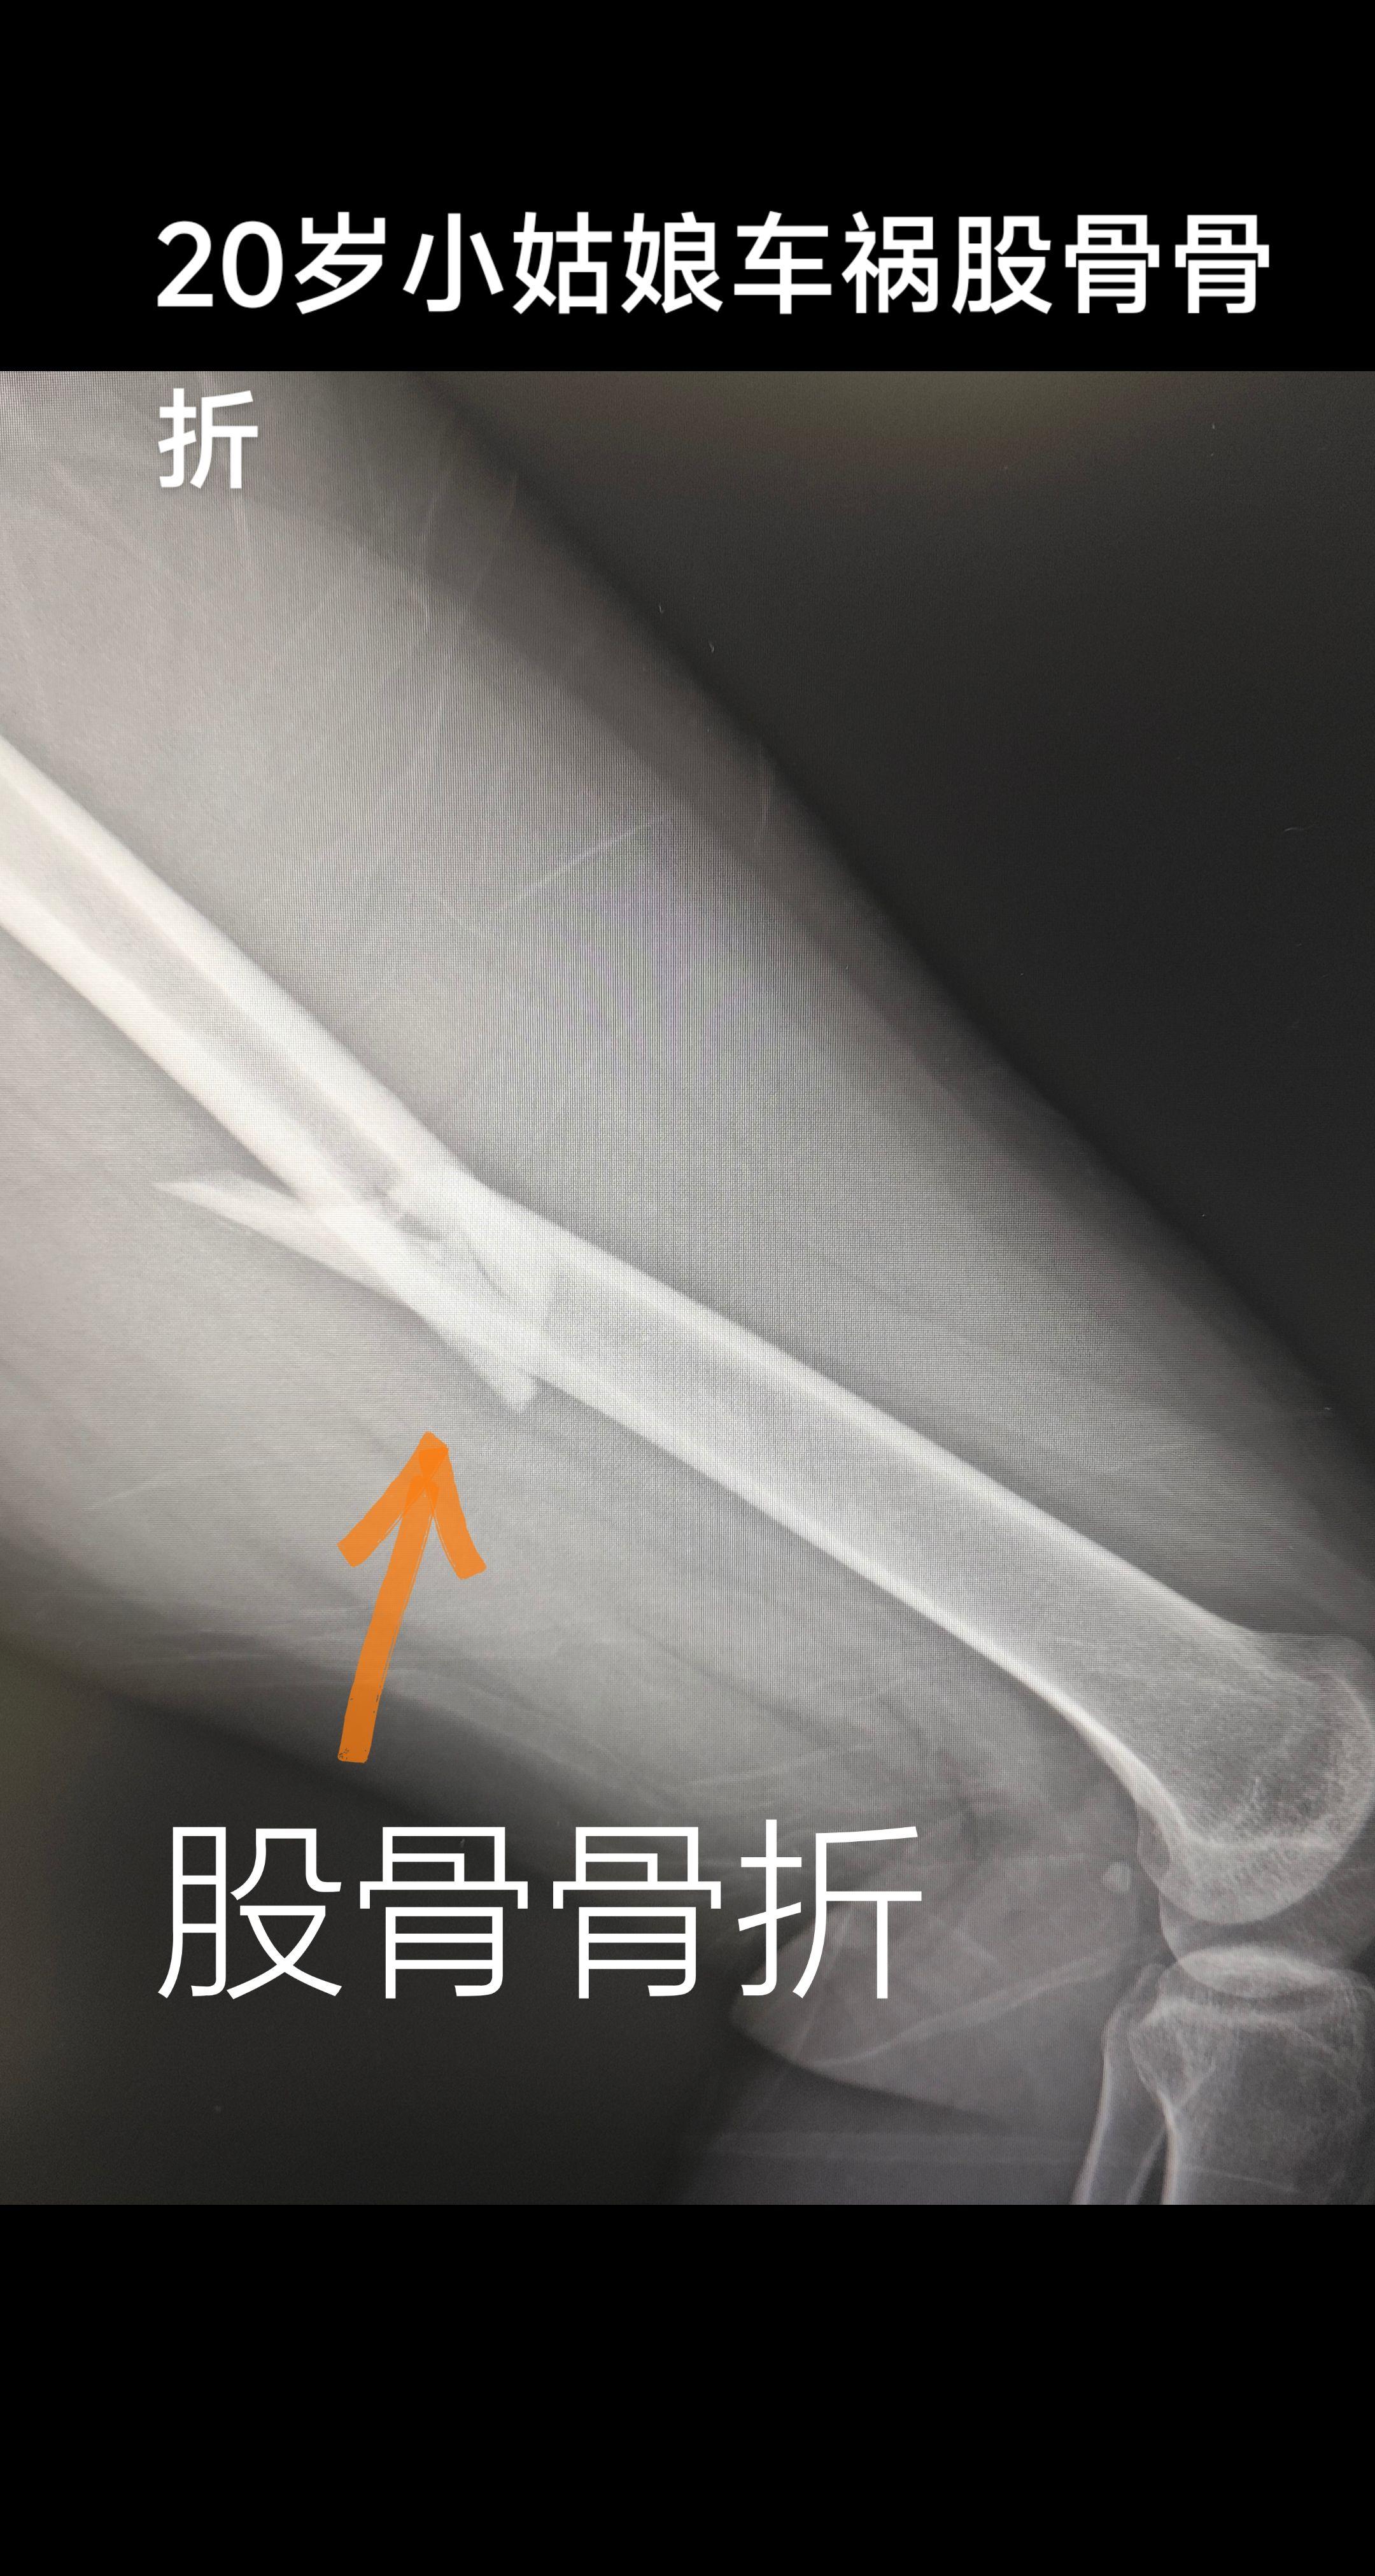

股骨骨折。